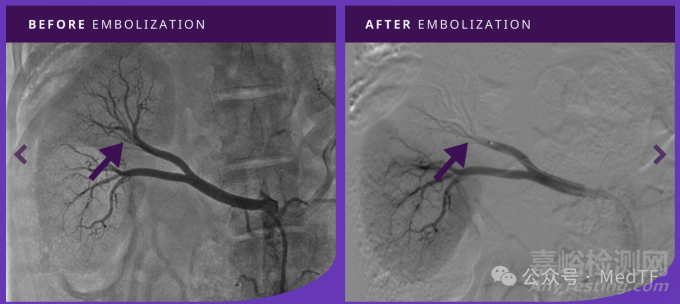

通過(guò)對(duì)豬腎動(dòng)脈栓塞,評(píng)估TEMBO效果Embocube。分別與麥瑞通的Embocube栓塞明膠和泰利福的Gel-Bead栓塞微球進(jìn)行對(duì)比。顯示出與Embocube、Gel-Bead相媲美的效果。

TEMBO栓塞右腎動(dòng)脈前后